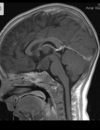

Qual é o padrão de Chiari II (arnold-chiari)

Deslocamento caudal das tonsilas cerebelares, do tronco cerebral, da medula oblonga, do IV ventrículo; Associação com Mielomeningocele; Craniolacunia (lesão radioluscente na calota); Disgenesia do corpo caloso Inserção baixa da tenda do cerebelo e baixa da tórcula (contrário de dandy), Herniação superior do cerebelo (com aspecto em torre), comprimindo o mesencéfalo e causando o tectum em bico. Clivus encurtado, fossa posterior pequena (contrário de dandy), curso anatomico alterado das artérias cerebelares postero inferiores (PAICAS); Anormalidades supratentoriais: Ventriculomegalia supratentorial, angulação anterior e inferior dos cornos frontais (aparência em asa de morcego), Colpocefalia (cornos occipitais maiores que os frontais dos ventrículos laterais), fenestração da foice cerebral (hipoplasica) com interdigitação dos giros corticais;